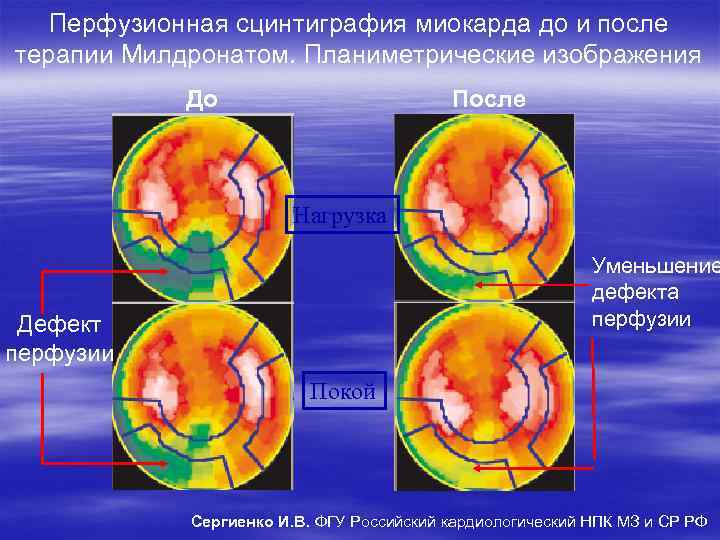

Перфузионная сцинтиграфия миокарда до и после терапии Милдронатом. Планиметрические изображения До После Нагрузка Уменьшение дефекта перфузии Дефект перфузии Покой Сергиенко И. В. ФГУ Российский кардиологический НПК МЗ и СР РФ

Перфузионная сцинтиграфия миокарда до и после терапии Милдронатом. Планиметрические изображения До После Нагрузка Уменьшение дефекта перфузии Дефект перфузии Покой Сергиенко И. В. ФГУ Российский кардиологический НПК МЗ и СР РФ